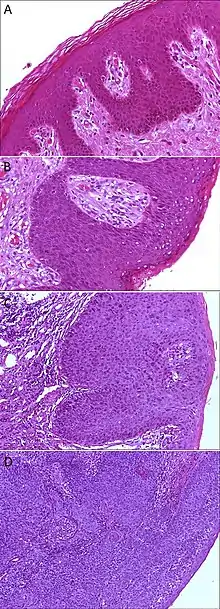

A. Normal histology, negative for anal intraepithelial neoplasia lesion (AIN)

B. Low-grade dysplasia, here called low-grade squamous intraepithelial lesion (LSIL)

C. High-grade dysplasia, here called high grade squamous intraepithelial lesion (HSIL)

D. Squamous cell carcinoma, infiltrating the stroma (middle and left in image), and HSIL (right in image)